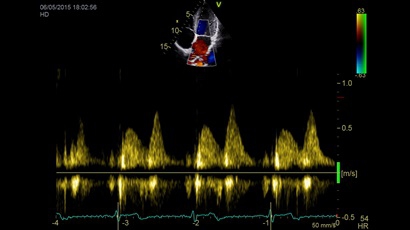

Тканевой допплер:

Да

Цветовой допплер:

Импульсно-волновой допплер:

TDI:

• Режимы: 4D, 2D (B-режим), цветной допплеровский режим, режим энергетического допплера, M-режим, цветной M-режим, спектральные режимы импульсно-волнового допплера (PW) и непрерывно-волнового допплера (CW), визуализация скорости движения тканей.